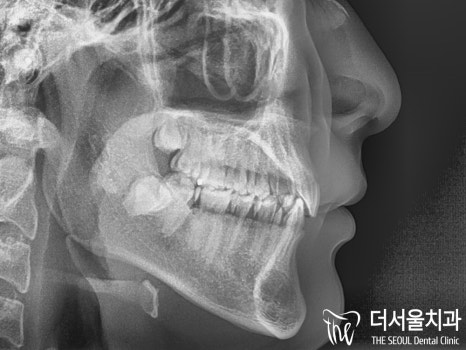

다행히 골격적인 문제는 없었으나

심한 딥바이트로 인해 저작이나 절단 등

치아 기능이 제대로 되지 않고 있었습니다.

이런 교합을 계속해서 내버려두게 되면

단순 치아 문제가 아니라

턱관절에도 좋지 않은 영향을 끼치게 됩니다.

본원에서는 윗니와 아랫니의 함입으로

교합관계를 긴밀하게 바꿔주면서

과개교합(Deep bite)를 개선시키기로 했습니다.